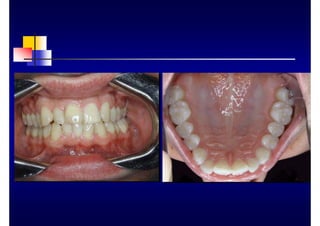

CLINICA

„ Bolsa ósea

„ Reabsorción ósea

„ Furcaciones: grados I, II, III

„ Movilidad y migración: grados I, II, III

Bolsa

„ Bolsa gingival

(relativa o falsa)

„ Bolsa periodontal

(absoluta o verdadera)

„ Supraósea

„ Infraósea

„ Simple

„ Compuesta

„ compleja